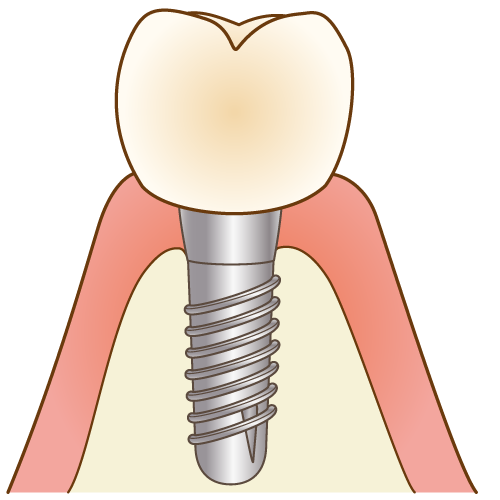

2-1:インプラントのメリット

インプラントのメリットは、大きく分けて以下の5つです。

- 天然の歯と変わらない噛み心地

→自分の歯のようにしっかりと噛めるため、食事の制限がほとんどありません。 - 見た目が自然で美しい

→周りの歯と調和し、美しい口元を取り戻すことができます。 - 周りの歯に負担をかけない

→ブリッジのように健康な歯を削る必要がありません。

→部分入れ歯のように、金具をかけることで周囲の歯にダメージを及ぼすこともありません。 - 顎の骨の吸収を抑制する

→インプラントは顎の骨に直接埋め込まれるため、骨の萎縮を防ぎ、顎の形状を保つのに役立ちます。これにより、顔の輪郭も維持されます - 他の治療法よりも長持ちする

→適切なケアを行えば、インプラントは長期間使用でき、場合によっては半永久的に使えます。

2-2:インプラントのデメリット・リスク

一方で、インプラントのデメリット・リスクは以下の5つです。

- 治療期間が比較的長い

→手術から被せ物の装着まで、数ヶ月の期間を要することがあります。 - 費用が高い

→インプラントは他の治療法(保険適用のブリッジや入れ歯)に比べて高額になることが多く、基本的に保険が適用されません。 - 外科手術が必要

→インプラントを埋め込むためには外科手術が必要であり、手術に伴うリスク(感染、神経損傷など)が存在します - 術後の腫れや痛み

→手術後、一時的に腫れや痛みが生じることがあります。ただし、処方された痛み止めや抗生物質をお飲みいただければ、痛みや腫れはかなり緩和されます。 - メンテナンスが重要

→インプラントは自然の歯と同様に、定期的なメンテナンスが必要です。これを怠ると、インプラント周囲炎などの問題が発生する可能性があります。

インプラント治療は、これらのメリットとデメリットの両方をよく理解・比較した上で、治療を検討することが重要です。